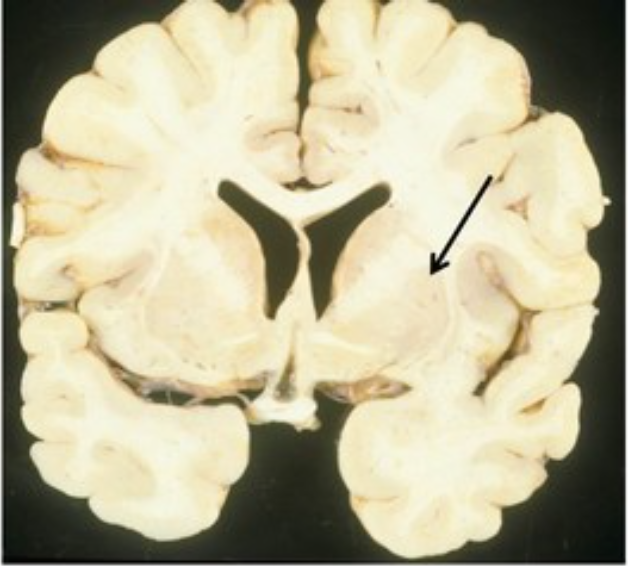

Identify

putamen

thalamus

temporal lobe